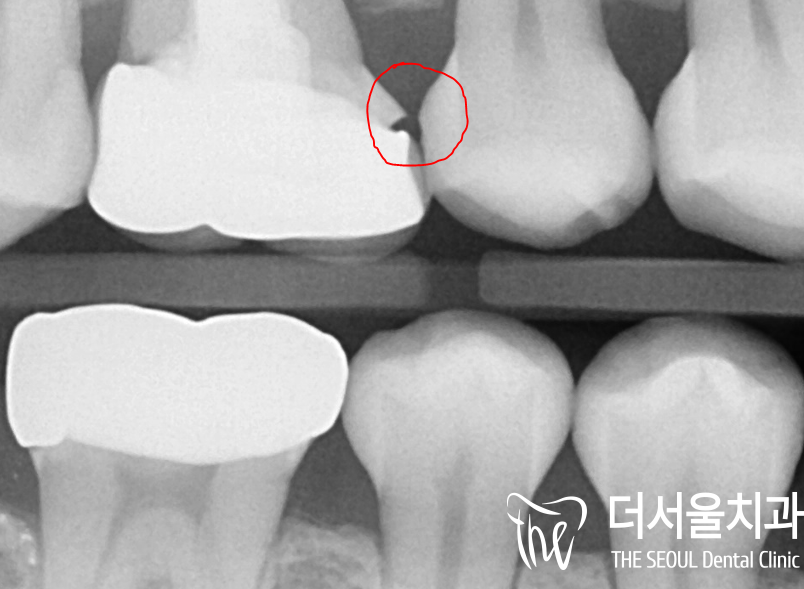

파노라마 사진을 보면

근관 내부가 충전재로 채워져 있는

어금니의 모습을 볼 수 있네요.

바로 이곳이 불편감의 원인이었는데요.

자세히 살펴보니 치조 백선이 사라질 정도로

치조골 소실이 나타나고 있었습니다.

*치조 백선 : 치조골 일부 테두리

정밀 검진을 통해 원인을 파악해 보니,

기존 보철 하방으로 약간의 틈이 생겨

우식을 비롯한 병소가 나타나 있었습니다.